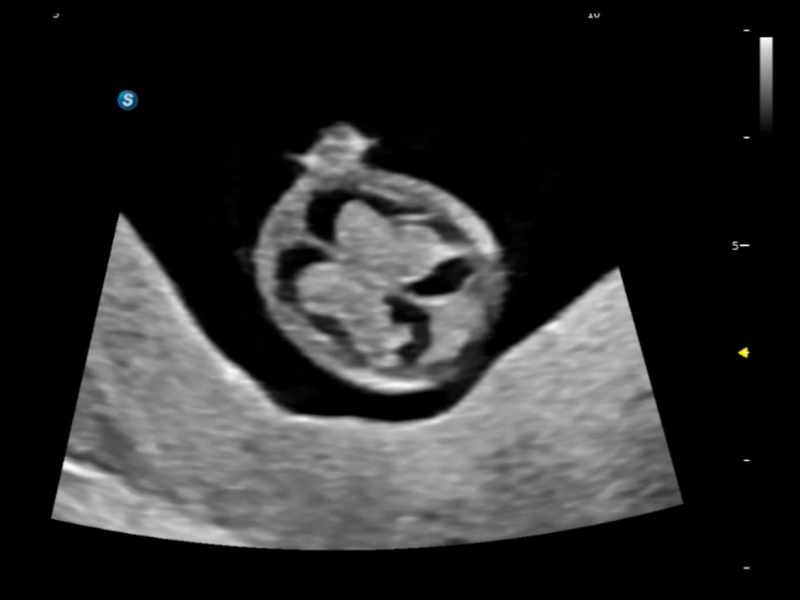

提供解剖示意图、标准超声图像、扫查手法图和操作者实时检查图像,指导操作者进行标准切面的正确扫查。